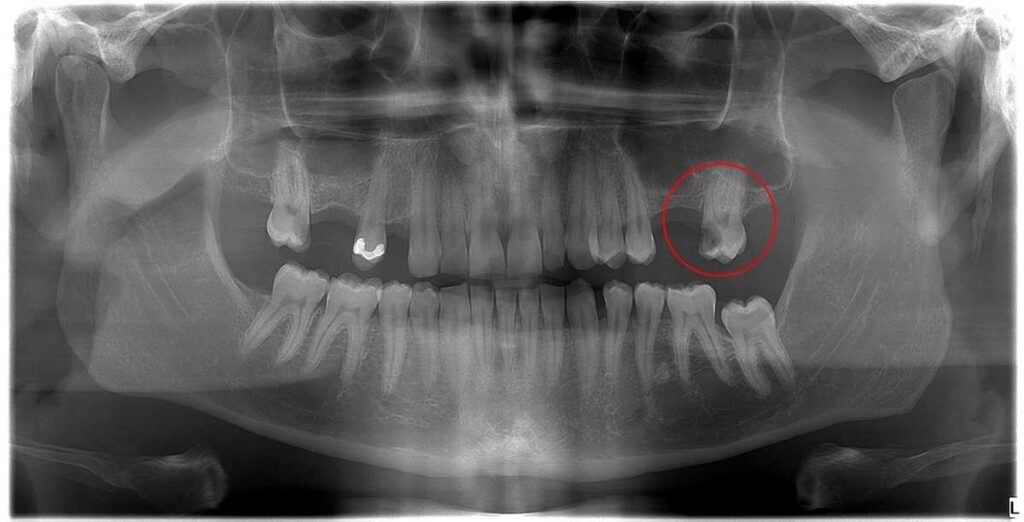

Dr. Molnár Katalin páciense arra panaszkodott, hogy foga érzékeny a hidegre és a melegre. A felvételen bekarikáztuk a fájdalmat kiváltó bal felső hetes fogat. Egy mély szuvasodás látható rajta, amely nagy kiterjedésű foganyag-veszteséget okozott. Nyilvánvalóvá vált, hogy az érzékenység hátterében ez a károsodás áll. A fog megmentéséhez gyökérkezelés szükséges. Ám a röntgenfelvétel A fog megmentéséhez gyökérkezelés szükséges. Ám a röntgenfelvételen az látható, hogy ennek a bal felső 7-es fognak - mint általában - 3 db foggyökere van, ám az első-külső (ún. mesio-buccalis) foggyökérben 2 db gyökércsatorna is található. Ezek feltárásához már mikroszkópos berendezést kell igénybe vennünk. Ez két lépésben történik: az első alkalommal megkeressük, feltárjuk, kitisztítjuk a csatornákat, majd ideiglenes, gyógyszeres töméssel látjuk el.